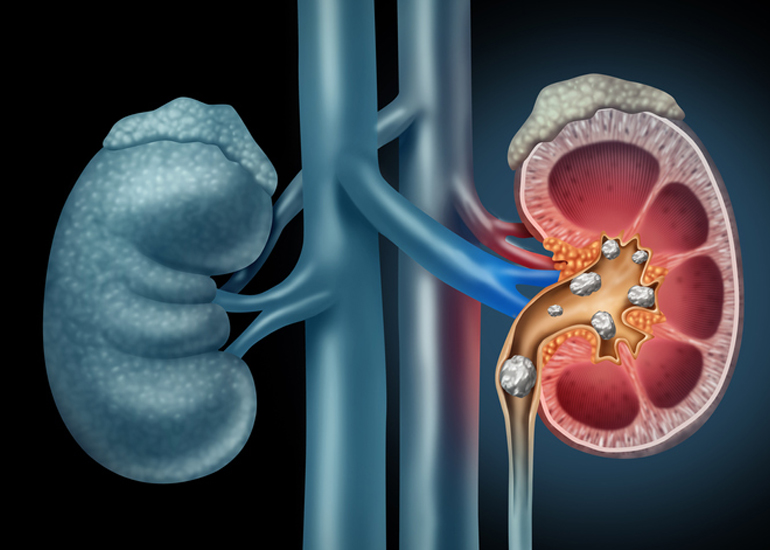

TREATMENT AVAILABLE FOR FOLLOWING DISEASES

Treatment Available